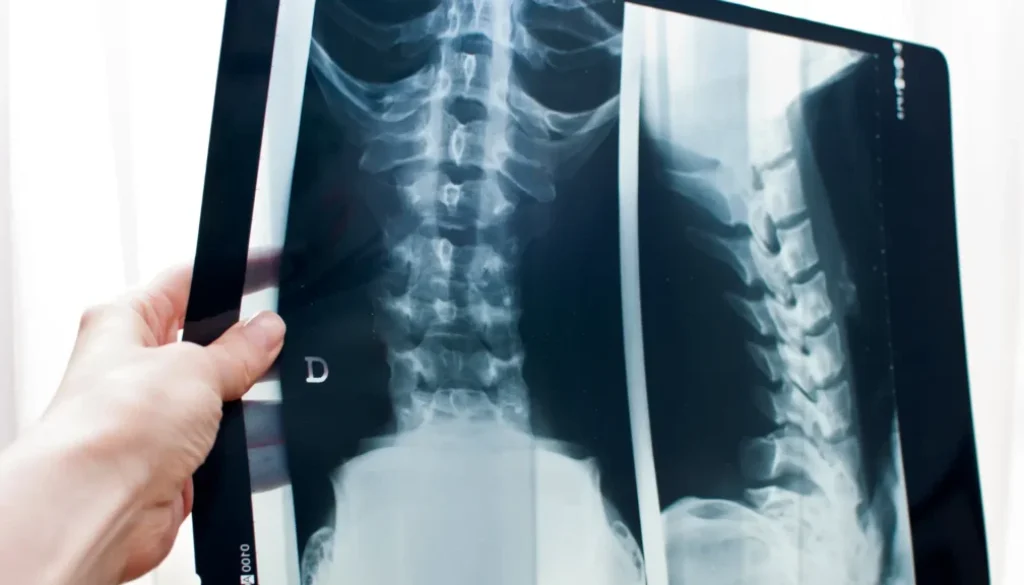

Want the Best Results From Your X-Rays? Here’s What Makes the Biggest Difference

“What can I do to make sure my follow-up X-rays show real progress?”

Bottom line: Your results aren’t just about what happens on the adjustment table—they’re also shaped by the small, consistent actions you take at home. The patients who commit to these tools and routines are the ones who see the biggest changes on their follow-up X-rays—and feel the difference in their day-to-day lives.